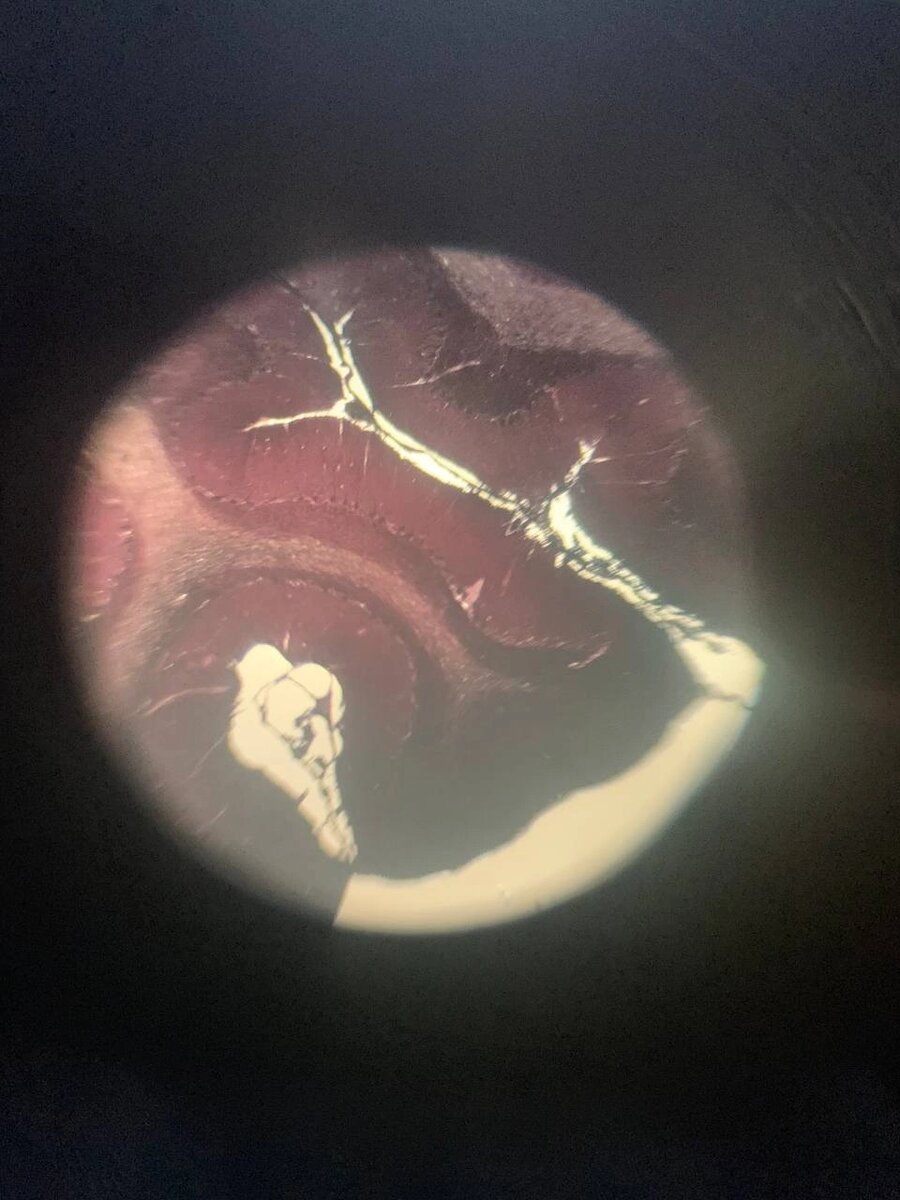

Задняя стенка глаза( прикиньте, там 10 слоев)